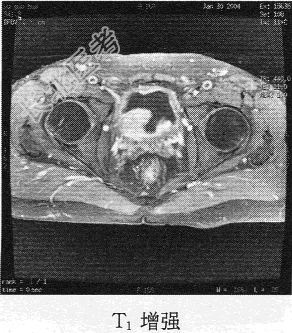

- 单项选择题患者男,76岁。反复无痛性肉眼血尿3个月, MR图像如下,最有可能诊断为

C、膀胱癌